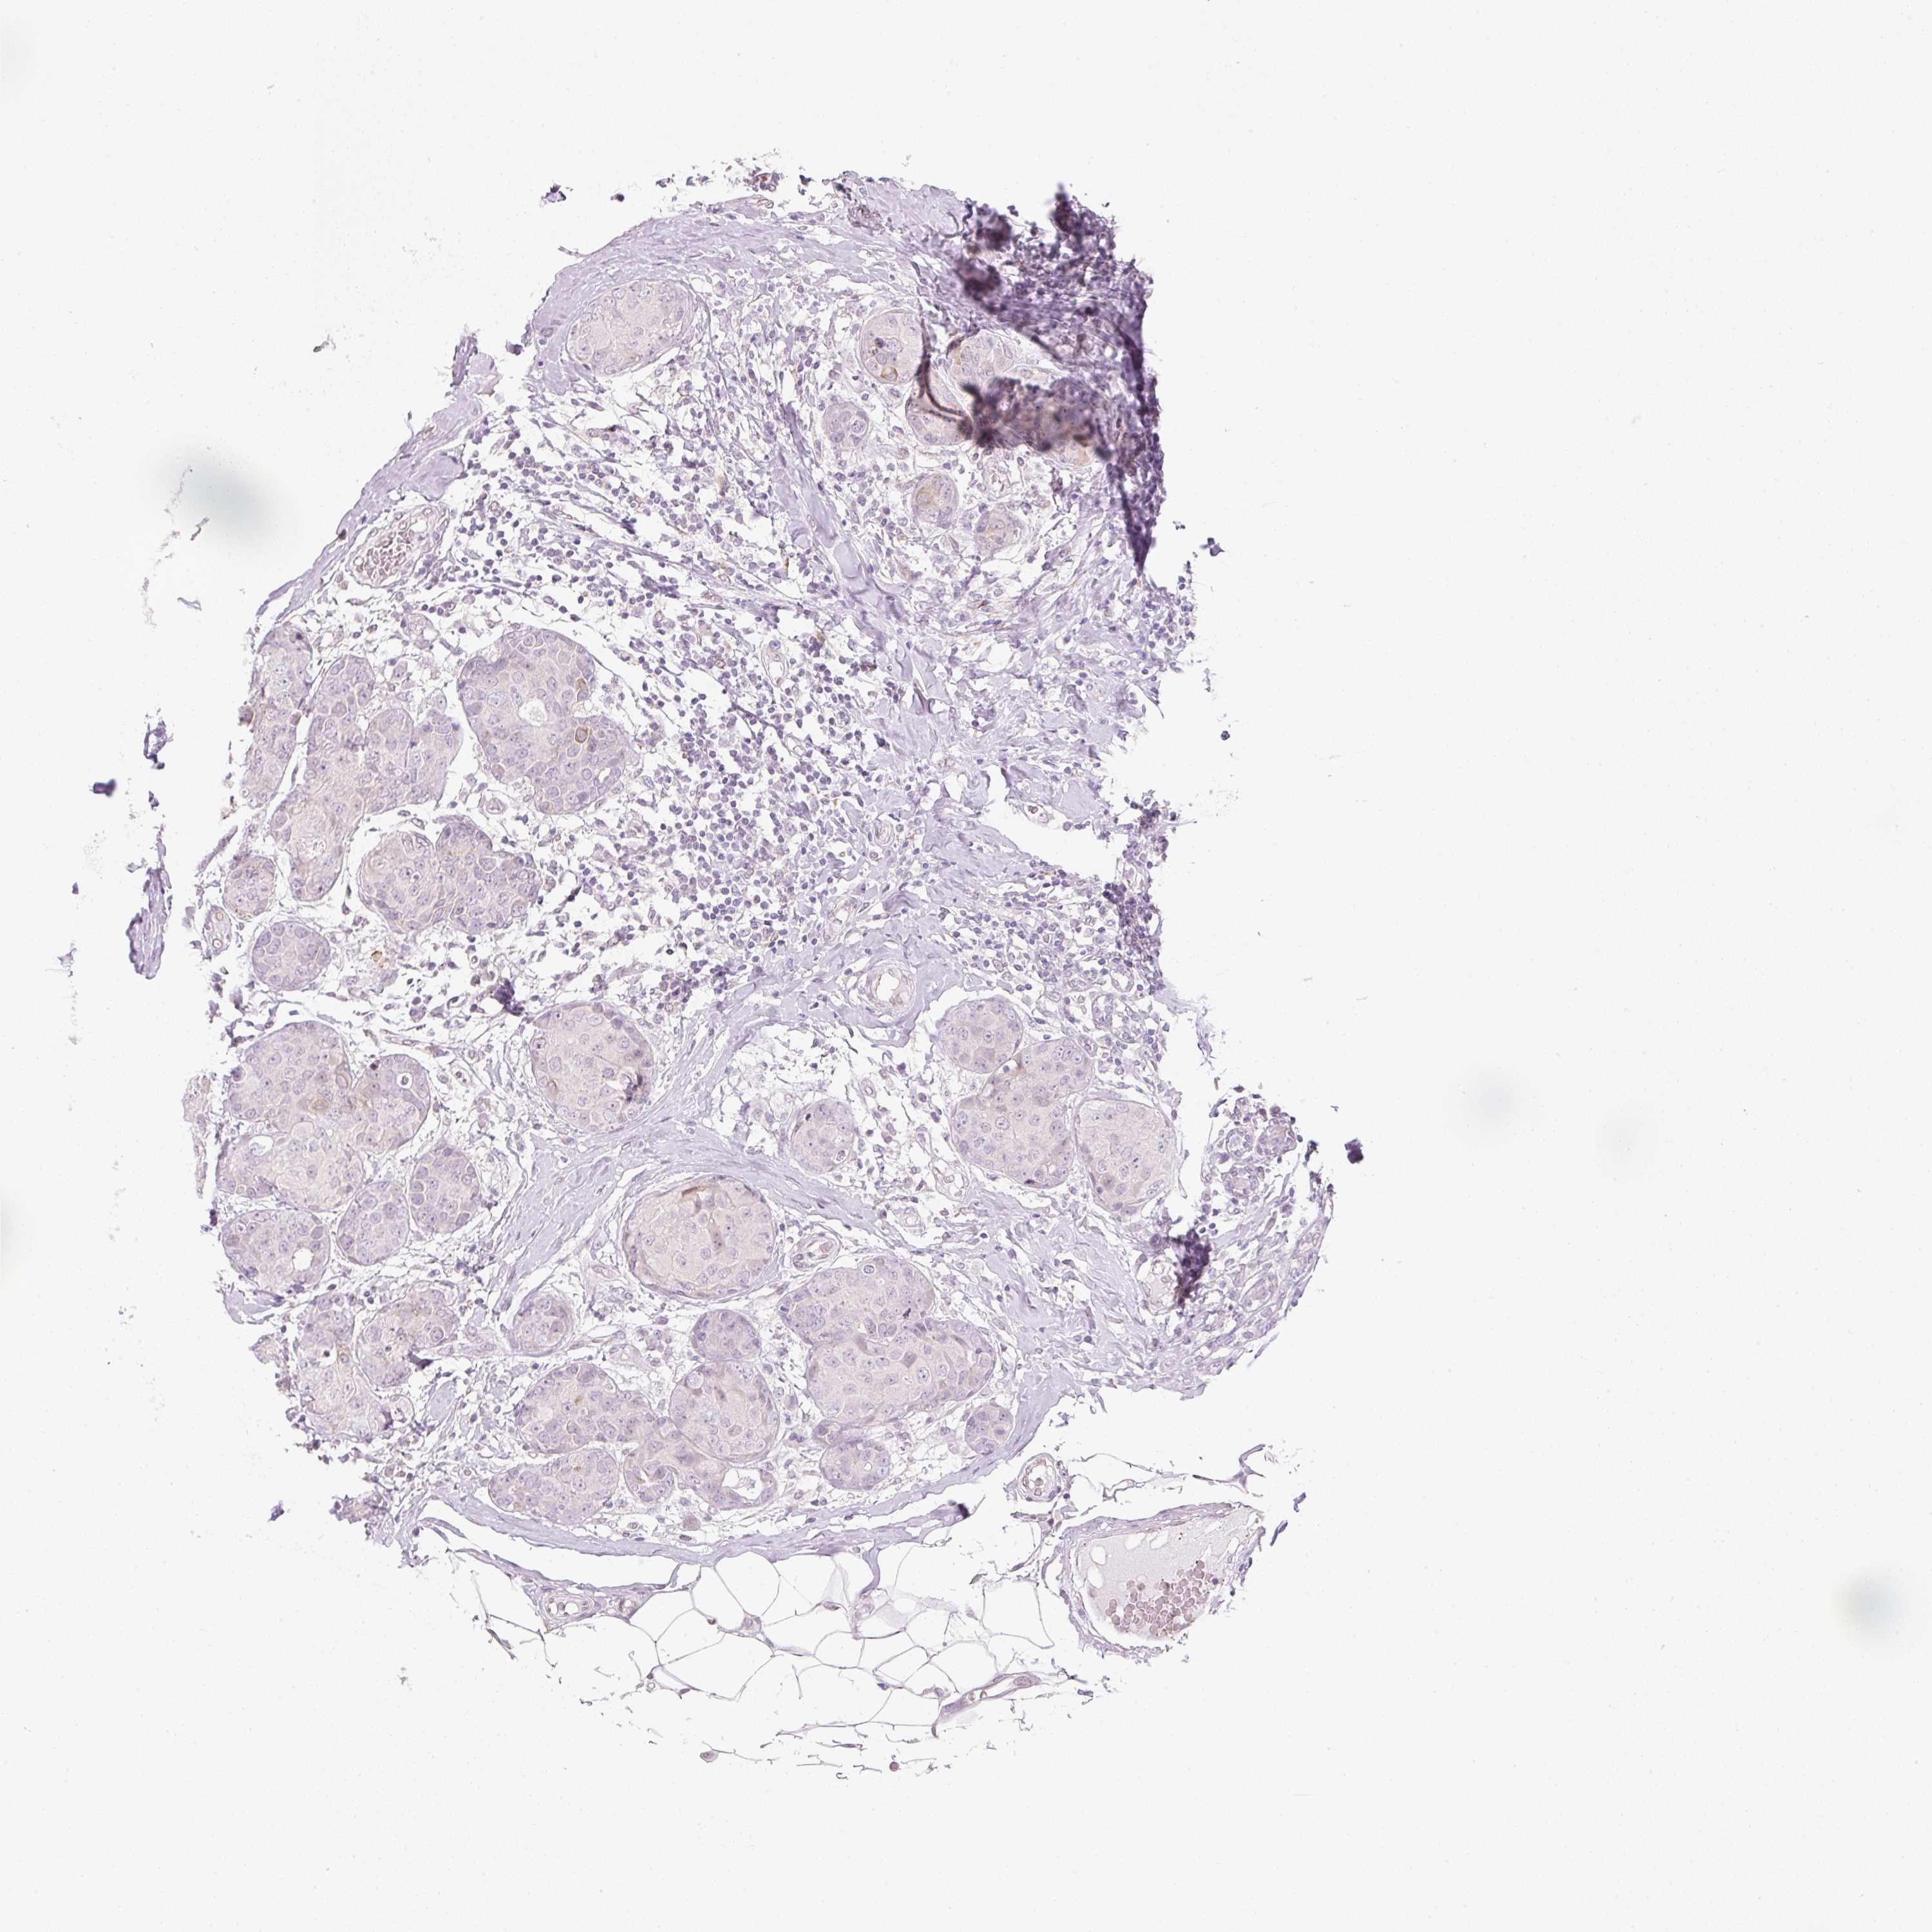

CANCER BREAST CANCER Show tissue menu

BRCA TCGA BRCA VALIDATION PROTEIN EXPRESSION